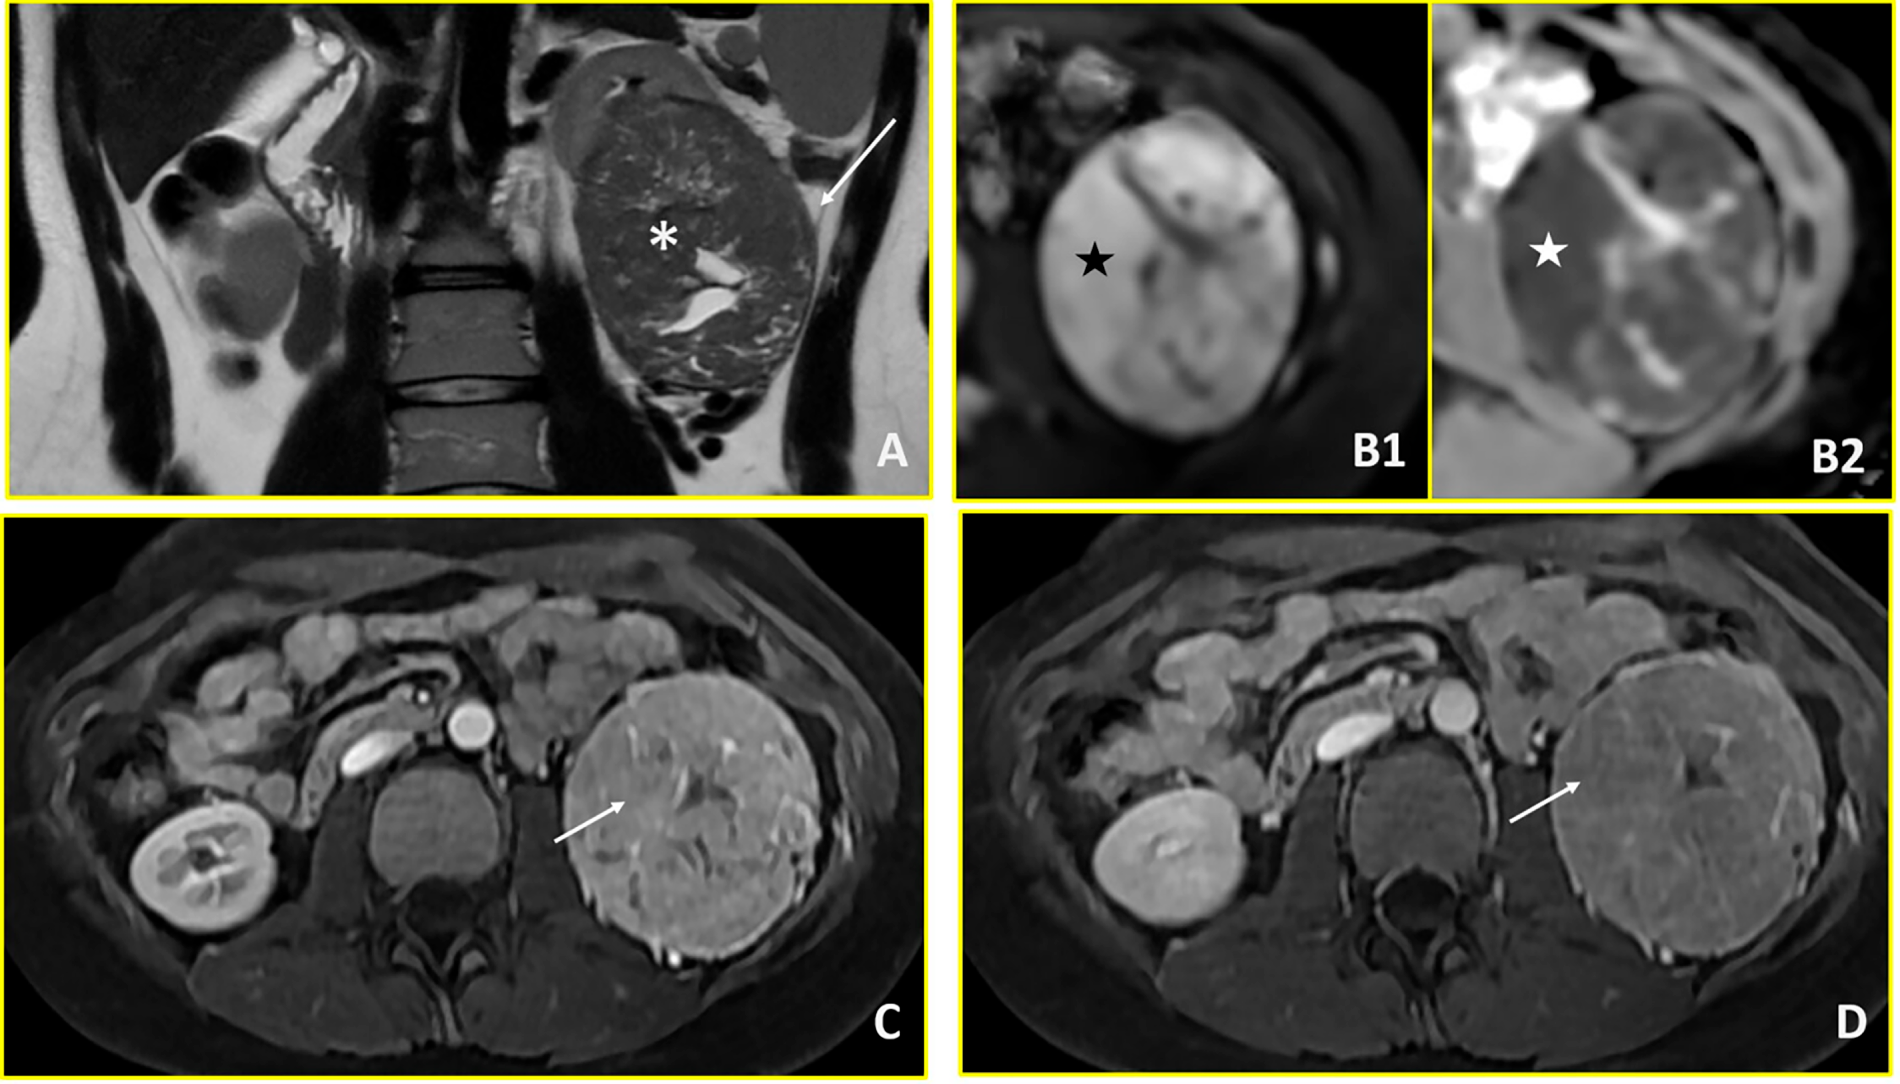

An 18-year-old female was admitted to the Department of Urology of Policlinico Gemelli with persistent abdominal pain, nausea, and diarrhoea. Initial ultrasonography, followed by abdominal CT, revealed a solid mass of approximately 11 cm at the lower pole of the left kidney, with central necrotic-cystic areas (Fig. 2). Thoracic CT excluded metastatic disease. Further abdominal magnetic MRI provided additional characterization, defining a left renal mass measuring 88 × 75 × 74 mm with well-defined margins and solid composition. MRI signal characteristics showed isointense T1 signal and hypointense T2W signal with hyperintense areas corresponding to fluid/necrotic components. Diffusion-weighted imaging demonstrated restricted diffusion (DWI/ADC). Post-contrast sequences revealed uneven enhancement due to fluid areas without impregnation, with the solid component appearing hypovascular compared to renal parenchyma. Notably, there was no washout in venous and late phases and no evidence of central scar—features that would be expected in typical clear cell RCC. The tumour demonstrated extension into the peri- and sub-renal adipose tissue without signs of extension beyond the retroperitoneum. Importantly, there was no contact with the renal artery or vein. Differential diagnoses included WT and RCC (see Fig. 2). Following discussion between oncologist, radiologist and urologist in a multidisciplinary board review, primary left radical nephroureterectomy was chosen over biopsy, considering the the age of patient. Definitive histopathological examination reported a diagnosis of RCC. Subsequent post-operative imaging excluded residual disease or recurrence. Based on the histological report and the complete removal of the disease, the was no indication for systemic treatment. Subsequently, clinical and instrumental follow-up was initiated, including physical examination, abdominal ultrasound and chest X-ray, as well as urine tests and blood tests including renal function, every three months for the first two years. Subsequent check-ups are expected to take place approximately every six months. Controls will continue for at least five years, considering RCC follow-up protocol.

Figure 2: Renal cell carcinoma (Case 2). Multiparametric MRI demonstrates a large left renal mass with imaging features characteristic of renal cell carcinoma. (A) T2-weighted axial image shows a hypointense mass in the left kidney (asterisk) with extension into the perirenal fat (arrow). (B1, B2) Diffusion-weighted imaging reveals restricted diffusion, characterized by hyperintensity on high b-value images (b = 800 s/mm2; black star in B1) and corresponding hypointensity on the apparent diffusion coefficient (ADC) map (white star in B2). (C, D) Dynamic contrast-enhanced imaging demonstrates avid arterial-phase enhancement (arrow in C) with subsequent washout on venous-phase imaging (arrow in D), consistent with the hypervascular pattern typical of renal cell carcinoma.